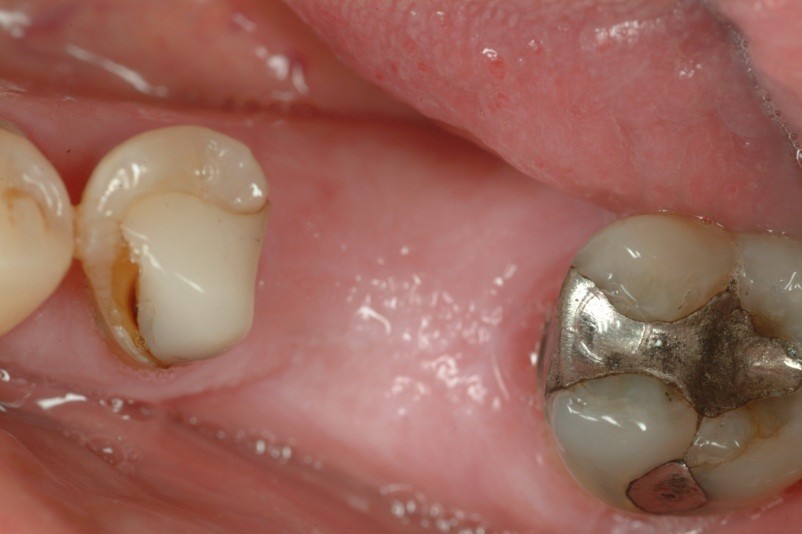

A toothache caused by a broken tooth (tooth fracture) without associated cavity or advanced gum disease. Biting on the area of tooth fracture can cause severe sharp pains. These fractures are usually due to chewing or biting hard objects such as hard candies, pencils, nuts, etc. Sometimes, the fracture can be seen by painting a special dye on the cracked tooth. Treatment usually is to protect the tooth with a crown. However, if placing a crown does not relieve pain symptoms, a root canal procedure may be necessary.